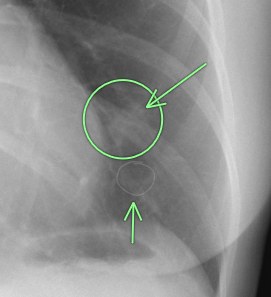

右肺の上方に1.5cm大の白い結節(○枠+矢印)が指摘されました。

胸部CTの3D画像で、右第2肋骨の骨折治癒像(○枠+矢印)であることが確定しました。